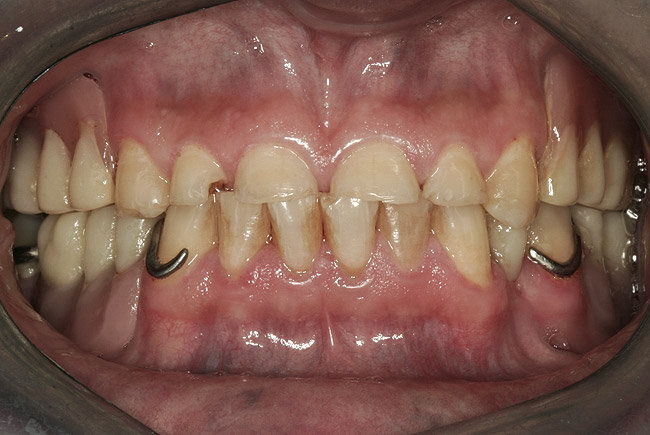

Initial examination revealed a partial edentulous patient with extensive wear of the maxillary anterior teeth and moderate wear in the mandibular teeth (Figure 1, Figure 2, Figure 3 , Figure 4, Figure 5, Figure 6 and Figure 7). The patient's maxillary and mandibular RPDs also showed excessive wear and multiple signs of fractures (Figure 2 and Figure 3). The patient had been wearing a mandibular nightguard for 8 years.

Figure 2  Intraoral occlusal view of maxillary dentition with the existing removable prosthesis presenting excessive signs of wear.

Figure 2

Figure 3  Intraoral occlusal view of mandibular dentition with the existing removable prosthesis presenting excessive signs of wear.

Figure 3